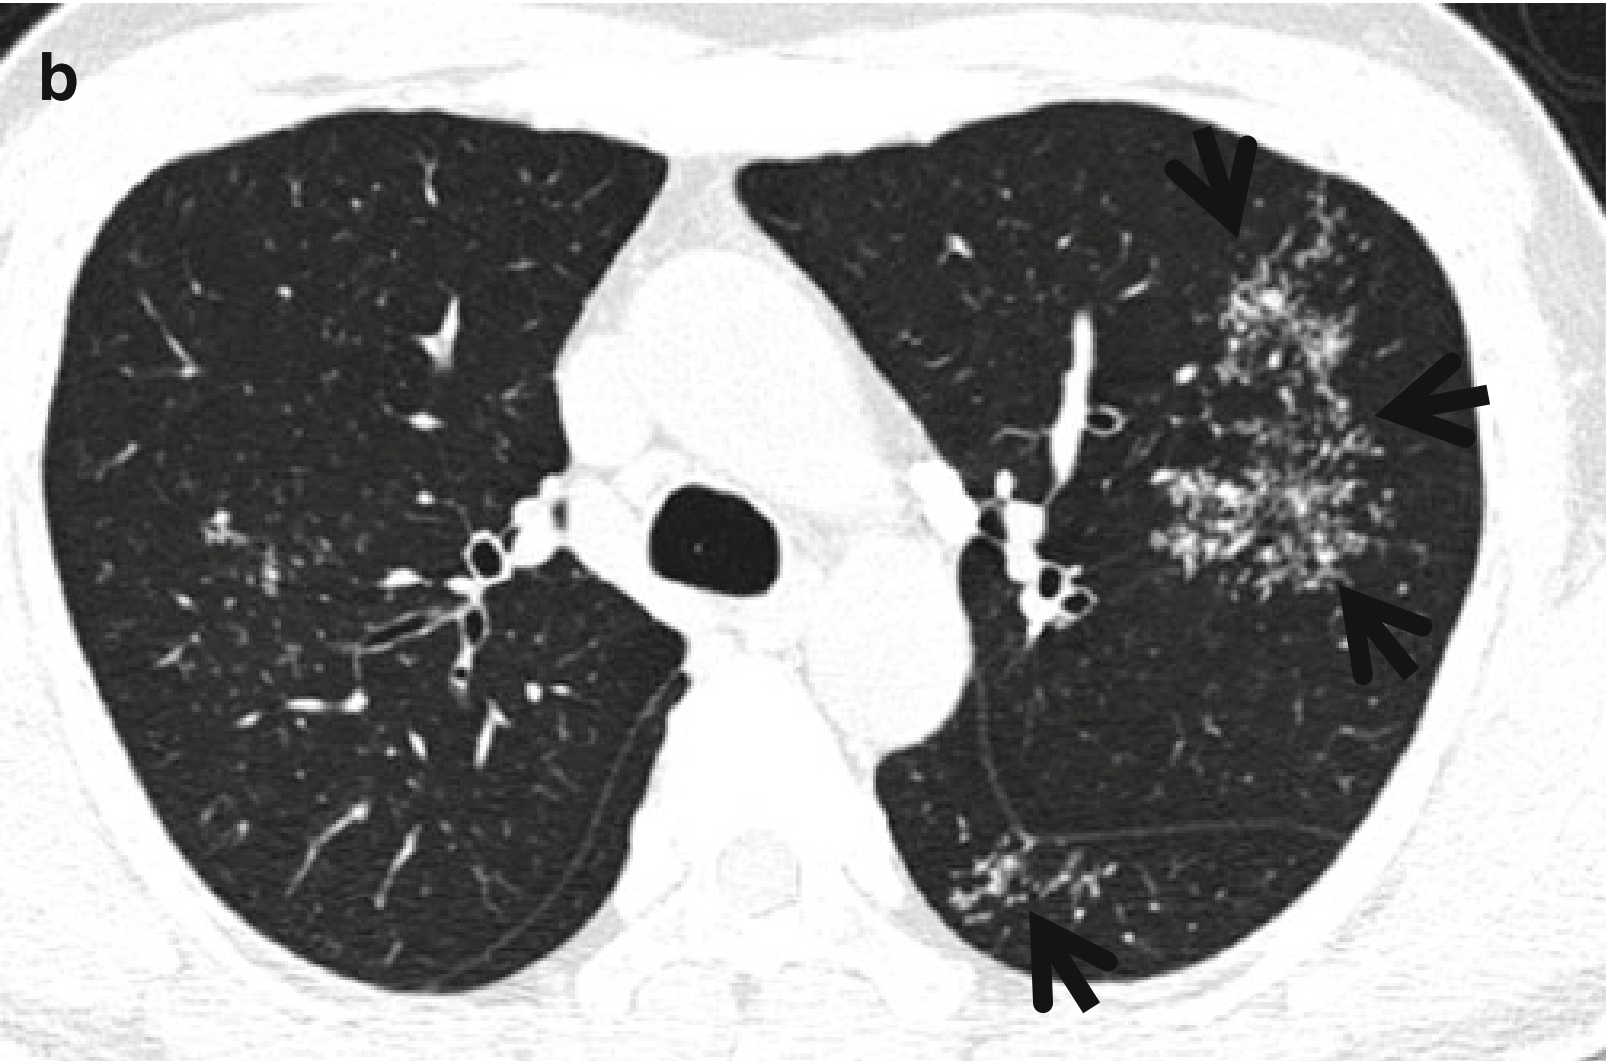

图3 CT星系征。男,53岁,活动性肺结核患者。薄层CT扫描(层厚=2.5mm)分别于主动脉弓水平(a)和奇静脉弓(b)水平肺窗示双肺上叶和左肺下叶背段的星系征(箭头所示)。